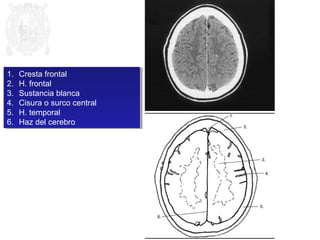

1. Cresta frontal

2. H. frontal

3. Sustancia blanca

4. Cisura o surco central

5. H. temporal

6. Haz del cerebro